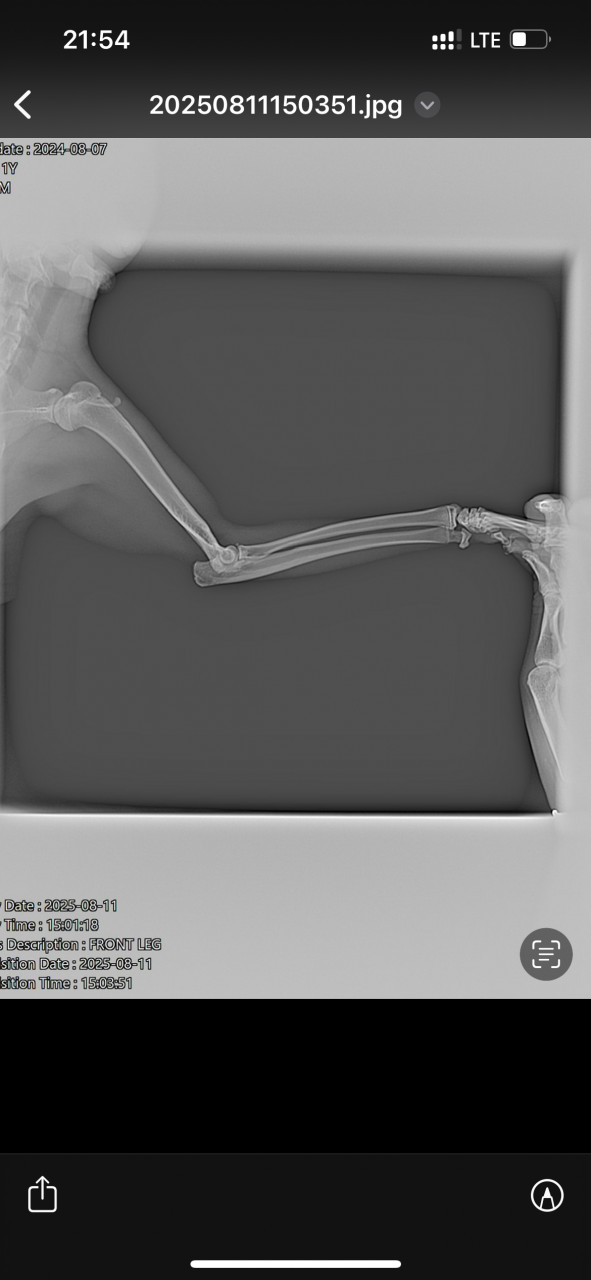

11.08 увидела, что он хромает, поехали на ренген. Сделали 3 снимка-без описания. Сказали колоть флексоарофен 0,3 в течении 3-5 дней. 17 числа опухла лапка в районе подушечки на левой ноге. Врач сказал колоть больше нельзя флексопрофен. 18 сегодня лапка не опухает, немного на неё наступает кот, до этого прыгал. Врач назначил Бонхарен или аналоги, нашла Хиовет в дозе 0,37 на его вес. Уточните, по снимку, что у кота? Стоит ли колоть Хиовет сейчас или подождать немного? Или вопрос к врачу ортопеду?

Здравствуйте. По рентгеновским снимкам у вашего кота отмечается перелом в области предплечья (лучевая и локтевая кости) с нарушением целостности и смещением. Это серьезная травма, которая требует консультации ветеринарного хирурга-ортопеда. Самостоятельно только противовоспалительными препаратами или хондропротекторами (Бонхарен, Хиовет) проблему не решить т.к нужна фиксация (операция или жесткая иммобилизация).

-Обратитесь к ветеринарному ортопеду или хирургу для выбора тактики т.к чаще всего требуется остеосинтез (пластины, спицы).

-Хиовет и аналоги применяются как поддерживающая терапия при суставных болезнях, но при свежем переломе они не дадут эффекта.

-До осмотра  ограничьте подвижность кота, держите в переноске или небольшом пространстве, чтобы не прыгал.

Лучше не откладывать и чем раньше будет выполнено правильное лечение перелома, тем выше шансы на полное восстановление лапы.